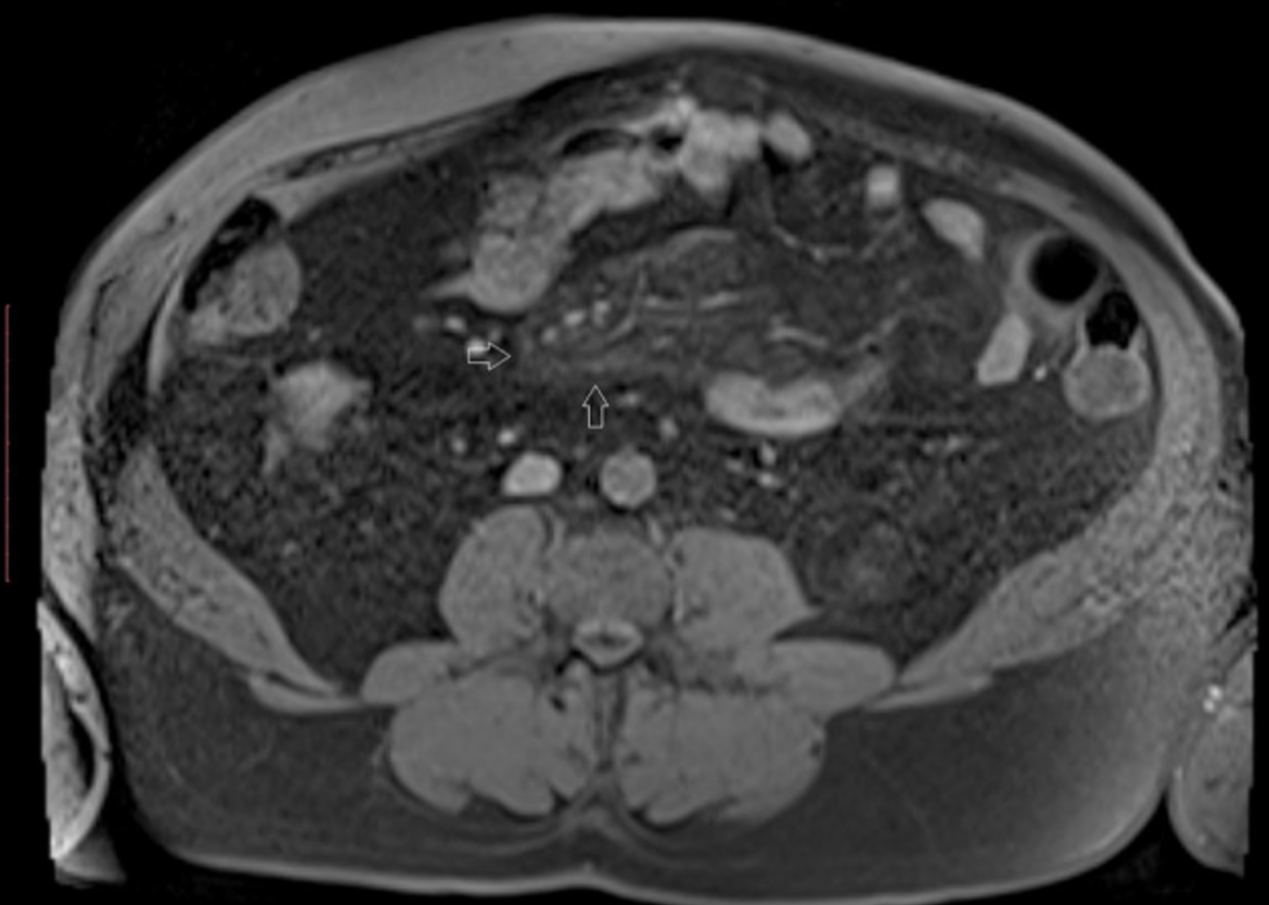

在随访中,经过2个月的糖皮质激素治疗后,患者报告腹痛减轻,MRI显示肠系膜异常明显减少(图2)。糖化血红蛋白水平降至8.8%(73mmol/mol),逐渐降低泼尼松的日剂量至5毫克/天。一年后,核磁共振显示肠系膜病变进一步消退。平均血糖水平在5–8.33 mmol/L范围内,周期性平均水平约为10 mmol/L。

图2